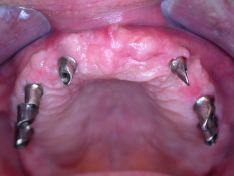

Il paziente è giunto alla mia osservazione con i soli 4 incisivi superiori, i quali presentavano una mobilità di terzo grado. Per questo si è resa necessaria l'estrazione. Il paziente è stato così sottoposto ad un intervento chirurgico implantologico in anestesia locale, in cui sono stati inseriti 7 impianti. Dopo 10 gg. sono state rimosse le suture e si è provveduto ad una protesi totale provvisoria. Dopo 12 settimane dalla chirurgia ho riaperto gli impianti e messo le viti di guarigione per il condizionamento dei tessuti. Attraverso una serie di passaggi, in tre settimane ho posizionato una protesi fissa in ceramica di 12 elementi.

Protesi totale superiore fissa su 7 impianti

Paziente uomo di anni 53 fumatore